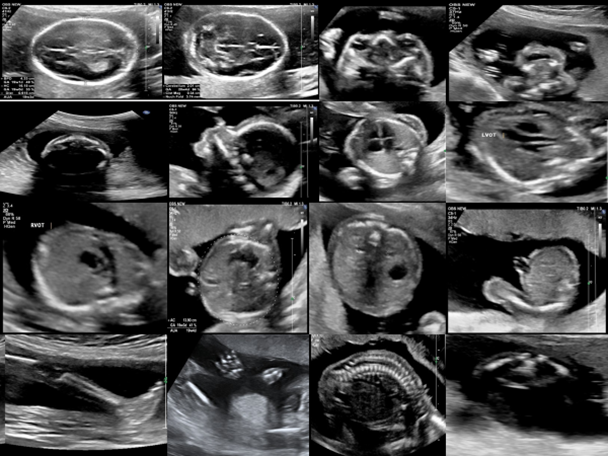

1. Enhanced Imaging Quality Target Scan produces high-resolution images, capturing minute details that are often missed in conventional scans.

2. AI-Driven Analysis The AI component analyzes scans with remarkable speed and precision, highlighting potential areas of concern for further examination.